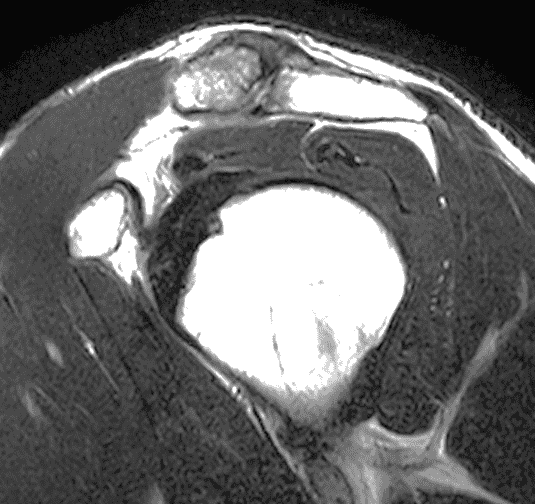

A 49-year-old male, avid weightlifter complains of chronic pain along the superior aspect of his right shoulder. He denies acute trauma. An AP radiograph (Figure 1A), as well as oblique coronal SPAIR (Figure 1B), axial fat-suppressed fluid sensitive (Figure 1C), and oblique sagittal T2-weighted images (Figure 1D) are shown. What are the findings? What is your diagnosis?

MRI: MRI is the primary imaging modality used for the diagnosis of DCO and identifies relevant findings earlier than radiographs or CT.  To differentiate DCO from similar conditions, it is important to identify underlying findings that are isolated to or more pronounced in the distal clavicle compared to other structures.  Osseous changes along both the acromial and distal clavicular margins of the joint often point to a different diagnosis.2

The principle MRI finding of DCO is distal clavicular marrow edema and surrounding inflammation on fluid-sensitive pulse sequences, especially with fat suppression (Figures 3 and 4).2, 9 Marrow changes can occur in patients with normal radiographs,10 in which case a term like “stress/overuse related marrow edema,” might be preferable to “osteolysis.” On MRI, more severe cases may show erosions or cysts in the distal clavicle and loss of the subchondral bone plate in addition to more pronounced marrow and soft tissue edema. A band of low signal paralleling the distal bone end may be present, suggesting a stress fracture line (Figure 5).8 However, a similar appearance can be due to the sclerotic rim surrounding distal clavicle cysts or small erosions (Figure 6). A small effusion or mild synovitis is often present in the AC joint.  Soft tissue edema within and surrounding the AC joint capsule and distal clavicular periosteum may be visible (Figure 3).  Some patients may also show marrow edema (or even erosions) in the anterior acromion, but the changes are typically more severe in the distal clavicle (Figures 5 and 7).2